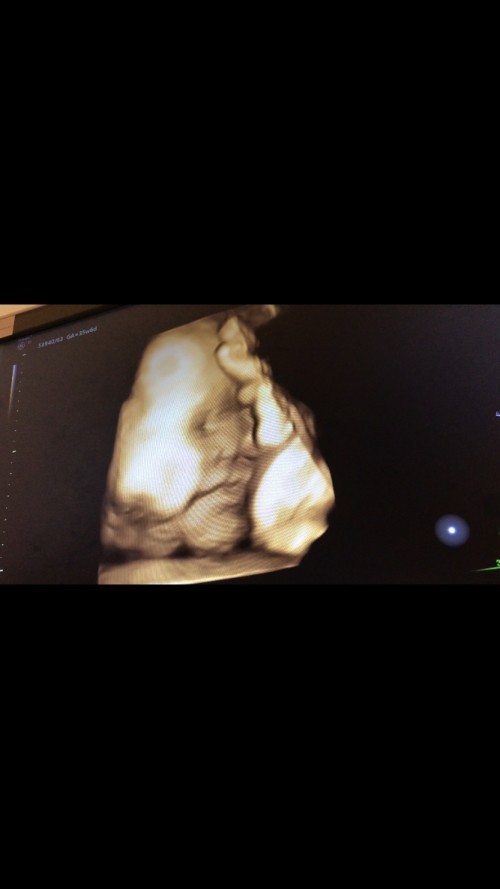

หนูน้อย 30 weeks